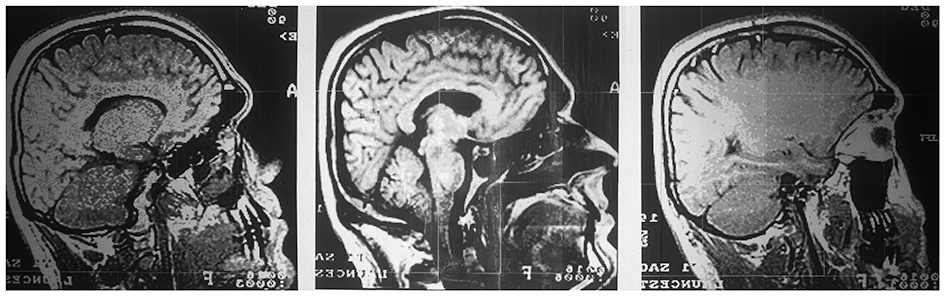

Prints from scans of the head.